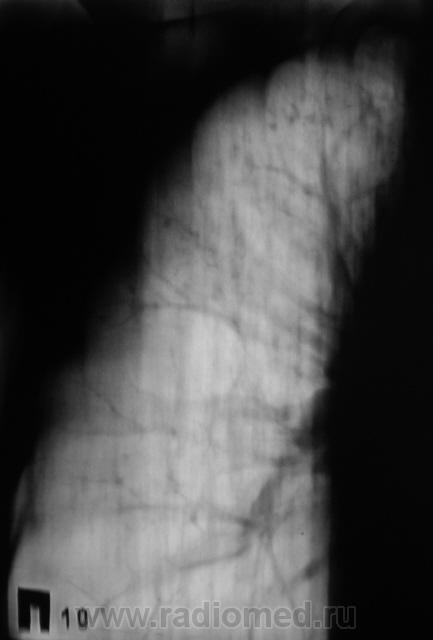

Повторили и "прямую", и произвели томограммы.

.....При гематогенном генезе подострого диссеминированого туберкулеза однотипная очаговая диссеминация локализуется в верхних и кортикальных отделах легких....

Мы тоже склонились в пользу диссеминированного.

Важно то, что мы "посылальщика" упаковали. Выставлен диссеминированный туберкулёз.